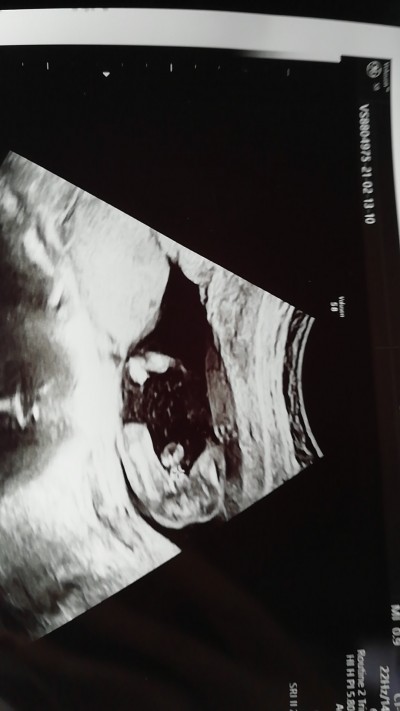

image

Doktor cinsiyetimizi söyledi ama degisir mi bu haftadan sonra kızlar

????

Gebelik haftası 14+4

11+4 iken bana kıza benzettim ddi ama kesin değil aramızda kalsın ddi. bugün 14+4 iken gittim erkek ddi ihtimal falan da demedi yani direk erkek ddi en sondaki Ultroson bacak arası mi acaba?

Sen birşey görebildin mi ben pek anlamadım zaten doktor da bak şu şu demedi